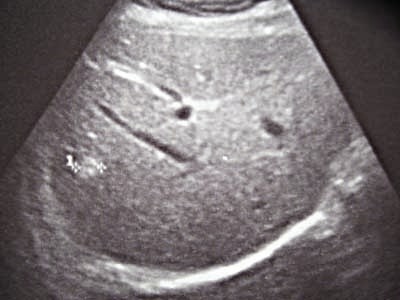

Женщина, 54года Профосмотр

Таких "штучек" у нее 7-8 по всей структуре печени(прошу прощения за качество снимков). Со слов, 2года назад было 3!

Заключение и дальнейшая тактика?